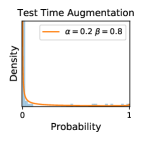

5.1 Distribution of Uncertainty Scores

Distribution of Uncertainty Scores Across Different Severity Levels As explained in Section 3, each uncertainty metric essentially defines an order/ranking among the data points. We conducted an analysis to better understand what data will be assigned high uncertainty under a particular uncertainty metric . Picking out the highest ranked data points (), we calculated the ratio of data points from each SL. Figure 4 summarizes the results as box plots for the Kaggle-DR and the Messidor-2 datasets; additional detailed statistics can be found in Table S.1 in the supplementary materials. From the plot and table, SL1 & SL2 examples account for a higher proportion among the top-ranked uncertain examples across the three ensemble methods. This finding matches our intuition that incipient disease examples (SL1 & SL2) are more likely to be considered uncertain by ensemble methods due to their ambiguity.

Uncertainty Scores on Out-of-Distribution Datasets As an additional experiment, we also tested the performance of the ensemble models on o.o.d. data inputs, which is a classic application of prediction uncertainties [1]. For this task, we produced distribution plots similar to those in Figure 4 for the previous experiment in our supplementary materials. The visualizations for the two o.o.d. image datasets can be found in Figure S.5 for ImageNet and in Figure S.6 for CIFAR-10. The results showed that the majority of o.o.d. data received higher uncertainty scores than in-distribution data for all three ensemble methods, suggesting that these ensemble methods would indeed perform well on o.o.d. detection tasks.

Comparing the three ensemble methods in Figure 4, the stacking ensemble method has the highest ratios of SL1 & SL2 data among the high-uncertainty examples it identified under both mean and var. TTA showed slightly better performance than MC-dropout but still falls behind the stacking ensemble method. Considering the fact that SL0 examples accounted for the majority of the dataset, the stacking ensemble method was much more precise (specific) in selecting truly ambiguous data points that were difficult to classify. From Figure 3, we can also see that the stacking ensemble method greatly outperformed the other two methods in finding false negatives under both mean and var uncertainty metrics.